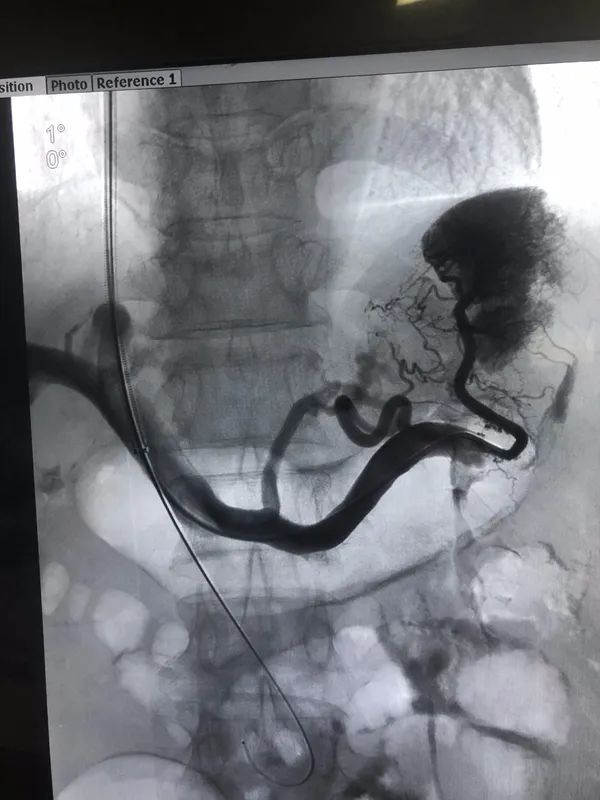

(tipss手术图解)"患者术后门静脉压力可明显降低,急症食管胃底静脉

2017年12月29日,在急诊手术tipss中,一针既穿中门脉.

病例1(tipss 胃-食管曲张静脉栓塞术)46岁男性患者,因"突发呕血600ml"

tipss治疗门静脉系统血栓一例